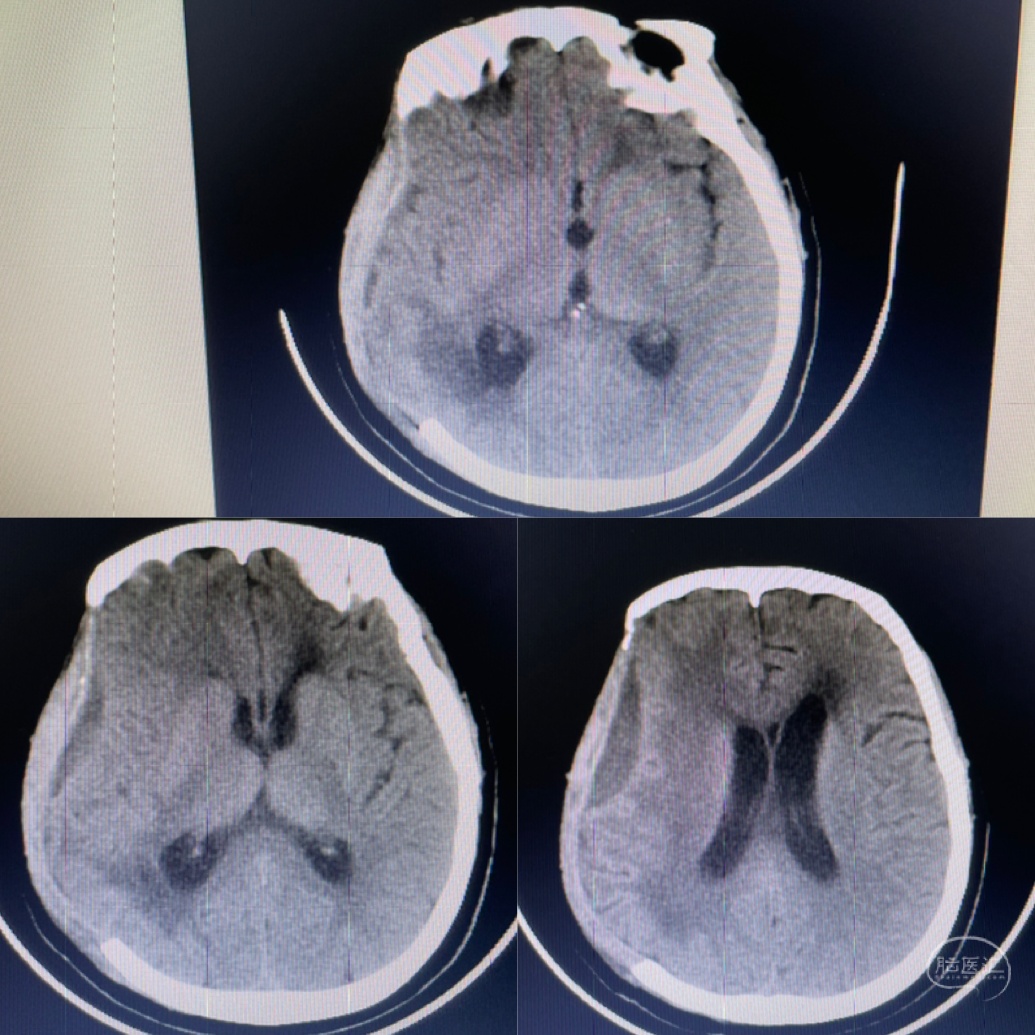

入院ct提示:右侧颞叶大量脑出血

颞叶血肿破溃形成硬脑膜下血肿

进一步增加脑出血颅内占位效应 颅内高压

术后第一天复查